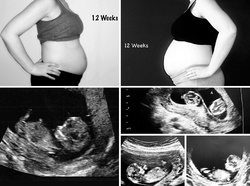

Am făcut câteva fotografii în care se pot vedea diferenţele de dimensiuni ale burţii mele, la fiecare dintre sarcini, dar şi dintre cei mici, în burtică, în diferite etape ale dezvoltării. Eu şi soţul meu încă suntem uimiţi de drumul pe care a trebuit să îl parcurgem pentru a avea copiii pe care astăzi îi ţinem în braţe. Nu aş schimba nimic, în ciuda durerilor şi a stresului prin care am trecut! Cei trei copii ai noştri, acum de 5 şi respectiv 2 ani şi jumătate, sunt lumea mea şi miracolele pe care nu le-aş fi trăit niciodată, dacă medicina nu ar fi fost atât de avansată. Pentru asta, suntem extrem de recunoscători!